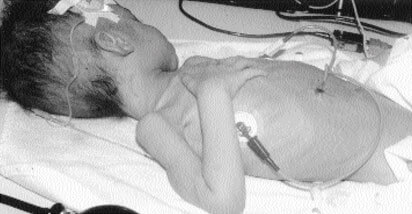

The following image depicts a child who has been neglected. He is severely underweight and has been diagnosed with failure to thrive. The signs of his malnutrition are evident, even in this picture.

Image #13:

Neglect: Failure to Thrive

Source: "AbuseWatch.net, n.d."